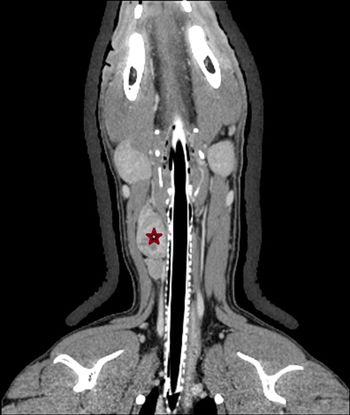

Dr. Caitlin Brown provides the anatomic pathology perspective on this challenging oncology case.

Dr. Lisa Viesselmann provides the clinical pathology perspective on this challenging oncology case.

Dr. Isabella Pfeiffer provides the radiation oncology perspective on this challenging oncology case.